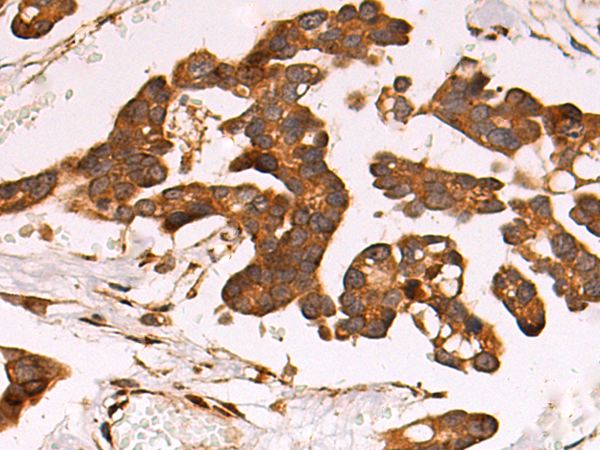

IHC positive control:

Human colorectal cancer and Human tonsil